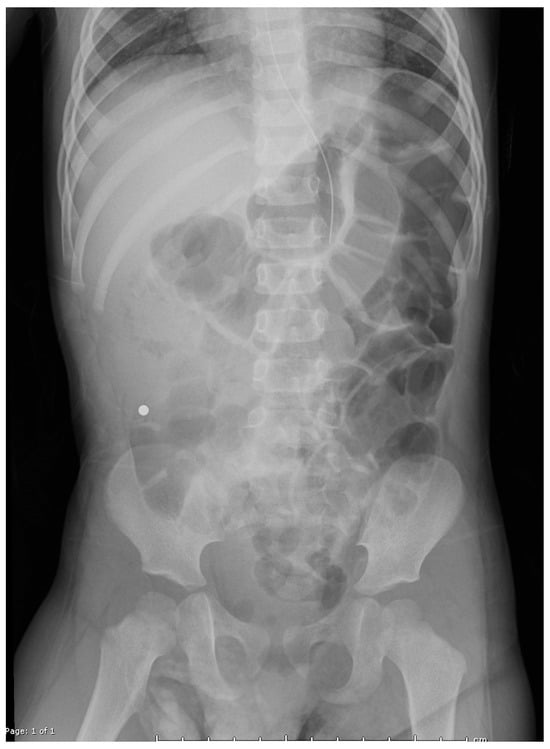

Interventions occurred across multiple anesthetic settings. Otolaryngology performed direct laryngoscopy, successfully removing two magnets adhered to the uvula with minimal trauma, consistent with findings from previous studies [4]. Gastroenterology then conducted an upper endoscopy, revealing a tightly clustered arch of 30 bb-sized magnets compressing the gastric incisura (Figure 2). Using a Roth net, they removed the magnets in two passes with no complications other than minor erosions on the gastric mucosa. Post-procedural imaging revealed residual magnets in the proximal jejunum (Figure 3).

Figure 3. Post-op abdominal radiographs revealed multiple magnets remaining in the proximal jejunum.